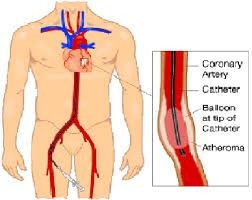

Overview

Package includes:

Days in hospital : 3 to 4 Days (For patient and one attendant)

Days in hotel : 7 Days (For patient and one attendant)

Room type in hospital : Shared

Room type in hotel : Private

Hotel category: Standard

Value added benefits of the Coronary Angioplasty:

Ø Doctor consultation charges

Ø Lab tests and diagnostic charges

Ø Room charges inside hospital during the procedure

Ø Surgeon Fee

Ø Nursing charges

Ø Hospital surgery suite charges

Ø Anesthesia charges

Ø Routine medicines and routine consumables (bandages, dressings etc.)

Ø Food and Beverages inside hospital stay for patient and one attendant.

Extra benefits:

ü Interpreter

ü Visa assistance

Ø Site tourism of the city

Ø Follow up with the doctor

Ø Airport pick up and drop

Ø Free online consultation with the doctor

Ø Priority appointments with the doctor

Ø Room upgrade from sharing to private

Overview

Package includes:

Days in hospital : 3 to 4 Days (For patient and one attendant)

Days in hotel : 7 Days (For patient and one attendant)

Room type in hospital : Shared

Room type in hotel : Private

Hotel category: Standard

Value added benefits of the Angioplasty PTCA :

Value added benefits of the Percutaneous transluminal coronary angioplasty (PTCA):

Ø Doctor consultation charges

Ø Lab tests and diagnostic charges

Ø Room charges inside hospital during the procedure

Ø Surgeon Fee

Ø Nursing charges

Ø Hospital surgery suite charges

Ø Anesthesia charges

Ø Routine medicines and routine consumables (bandages, dressings etc.)

Ø Food and Beverages inside hospital stay for patient and one attendant.

Extra benefits:

ü Interpreter

ü Visa assistance

Ø Site tourism of the city

Ø Follow up with the doctor

Ø Airport pick up and drop

Ø Free online consultation with the doctor

Ø Priority appointments with the doctor

Ø Room upgrade from sharing to private